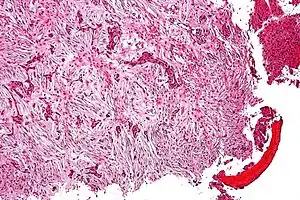

| Micrograph of an adamantinoma showing the biphasic histomorphology. H&E stain.. | |

Histologically, islands of epithelial cells are found in a fibrous stroma. The tumor is typically well-demarcated, osteolytic and eccentric, with cystic zones resembling soap bubbles.[2]